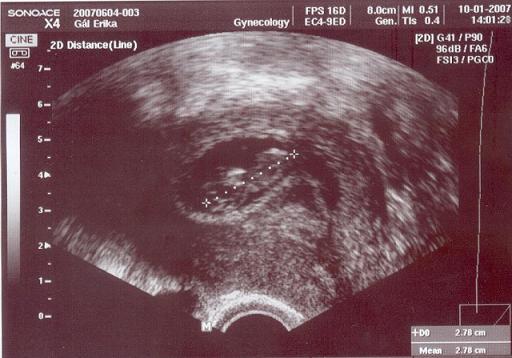

Nos, hát megvolt a mai UH, végre valahára, lelkem ismét nyugovóra térhetett :roll: Azért féltem tőle, hisz' még a tüske bennem van, de talán már kicsit kopott a hegye.. De nem teljesen :roll:

Mindent a legnagyobb rendben talált a Dr. bácsi :wink: a másik petezsákocska szinte teljesen felszívódott, és képzeljétek, a haematómát is szinte teljesen sikerült eltűntetnem az elmúlt 11 napban. Bizony megérte az a rengeteg fekvés :oops: :roll:

A legnagyobb hír, és ez számomra a legcsodásabb, hogy azóta megduplázta önmagát, CRL-je 2,78cm, és most valószínüleg pihenhetett, mert simán meg tudtuk nézni a szívhangot, erőteljes, tiszta, szabályos :roll: Majd teszek fel képet, bár igazán a szakavatott szemek látják a lényeget :D